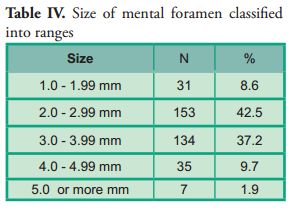

The size of the mental foramen was classified into five measuring ranges. Most (n=153; 42.5%) were included in the 2 mm to 2.99 mm range on both sides. No significant differences were observed compared with the contralateral side (p*0.623) (Table IV).

The size of the mental foramen was classified into five measuring ranges. Most (n=153; 42.5%) were included in the 2 mm to 2.99 mm range on both sides. No significant differences were observed compared with the contralateral side (p*0.623) (Table IV).

The size of the mental foramen was classified into 5 ranges. In most cases, they were located in the 2 mm to 2.99 mm range on both sides, with a frequency of 75 cases (41.7%) on the right side and 78 cases (43.3%) on the left side.

Several authors have evaluated the size of the mental foramen on dry mandibles. Their results are similar to the results of this study: within the 2 mm to 2.99 mm range (Table VII).

The size of the mental foramen was classified into 5 ranges. In most cases, they were located in the 2 mm to 2.99 mm range on both sides, with a frequency of 75 cases (41.7%) on the right side and 78 cases (43.3%) on the left side.

Several authors have evaluated the size of the mental foramen on dry mandibles. Their results are similar to the results of this study: within the 2 mm to 2.99 mm range (Table VII).